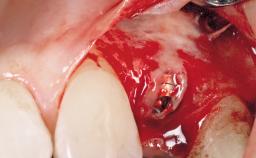

Immediate Placement of an Implant in a Maxillary Right Central Incisor Site

A 30-year-old female patient was referred to the office for the treatment of tooth 11. Her chief concern at the initial visit was to inquire, “Why is my tooth pink?” Upon clinical examination, it was determined that tooth 11 had a previous history of trauma and that the clinical crown had become noticeably pink in color as a result of internal resorption. This diagnosis was confirmed radiographically, indicating a large radiolucency involving the central and distal portions of the clinical crown. It was determined that restoration of this tooth was not possible, and that extraction was indicated. The presence of a mid-line diastema, which the patient wanted to reproduce, directed the treatment plan for tooth replacement utilizing a dental implant.

| Placement Protocol | Immediate implant placement |

| Tooth Site | Maxillary incisor or canine |

| Socket Morphology | Single-root socket |

| Socket Integrity | Sufficient, with intact bone walls |

| Bone Volume | Sufficient, with intact walls |